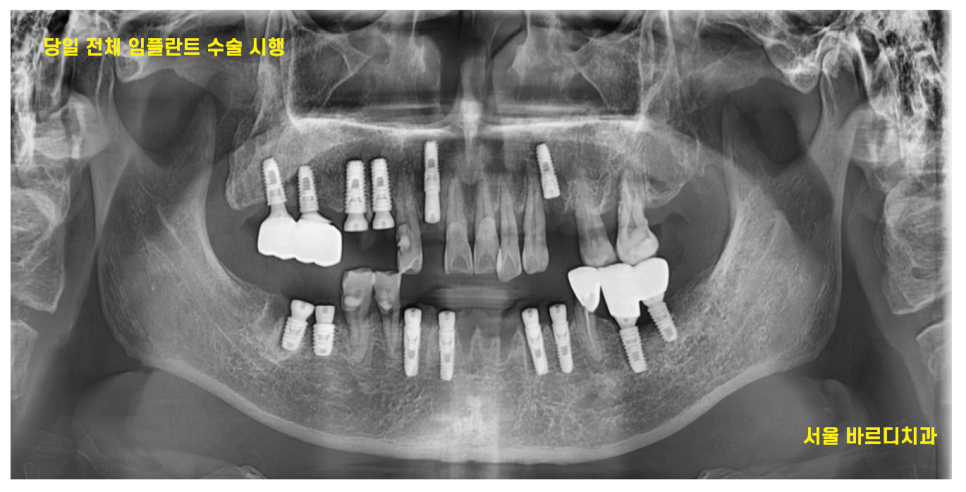

24.05.08

전반적으로 강일동 임플란트 치료가 필요할 때에는

치료 순서를

-

위 , 아래로 나눈다

좌,우로 나눈다.

하루에 전악을 수술한다.

3가지로 나뉘게 되는데요.

환자분은 이왕 치료해야하면

한번에 치료하고 싶다고 말씀해주셨습니다.

당일에 10개의 임플란트 식립으로

치료 계획을 수립

미리 CT를 통하여

식립 예정 부위를 분석하였기 때문에

하루에 다수 치아 수술이 가능했습니다.

강일동 임플란트 10개 식립

문제 없이 끝내드렸습니다 .